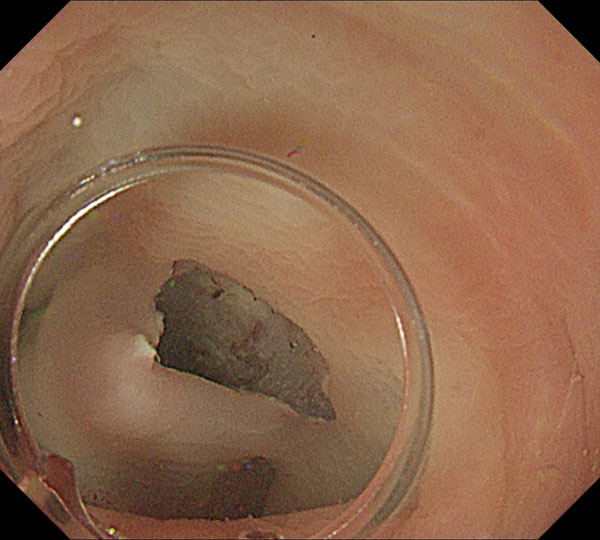

7. 十分に剥離したのち、残った粘膜を切開し切除が終了しました。

8. 切除標本です。筋層直上で切除しているので、病理学的評価が詳細に行え、根治度の判定が正確に行えます。